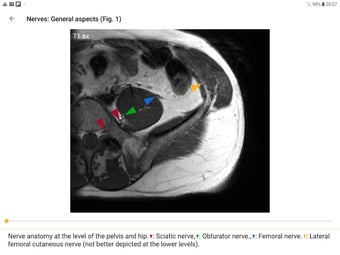

Die Pro-Version enthält mehr als 4.000 hochwertige Bilder von herausragender Bildqualität, die den Text veranschaulichen. Sie sind so konzipiert, dass sie dem Leser einen schnellen Überblick über die wichtigsten Informationen zum Zustand geben.